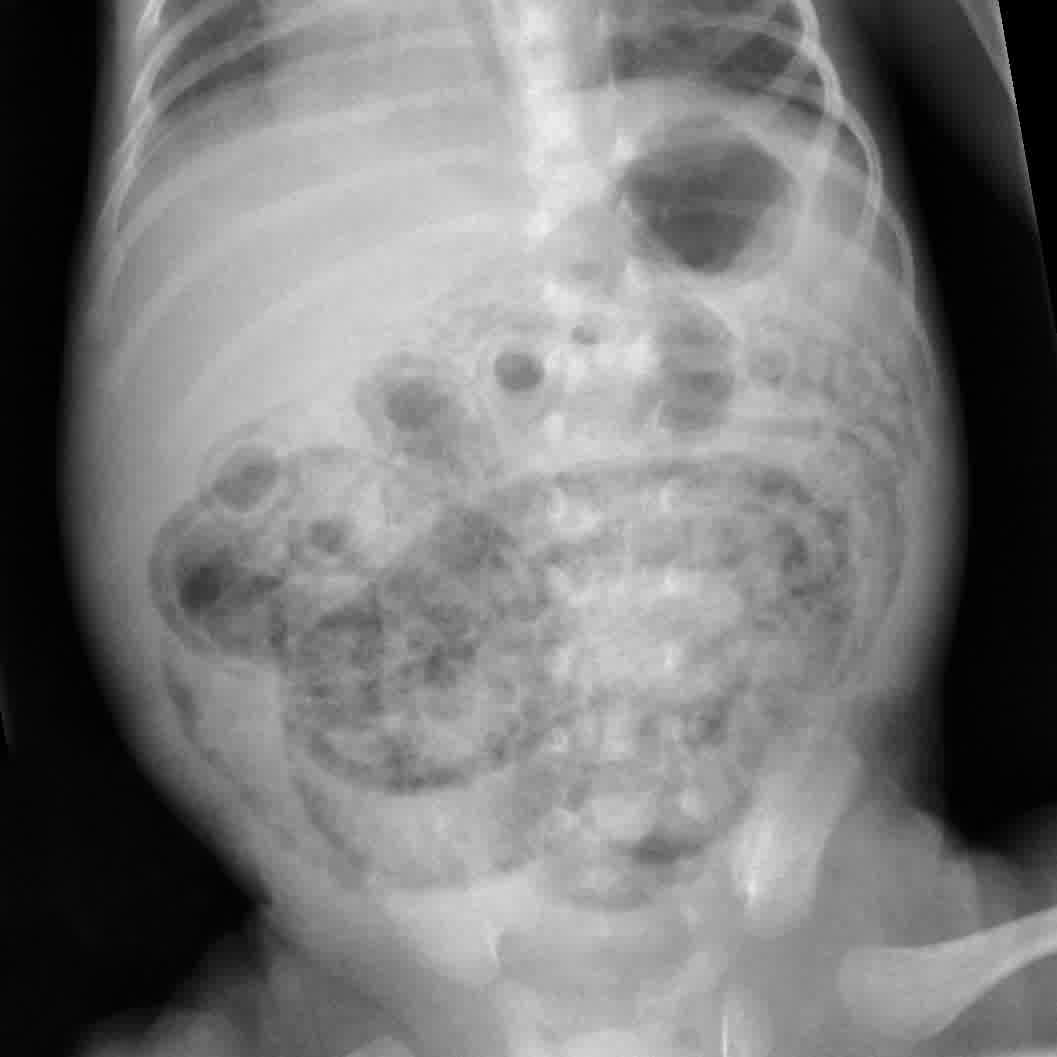

From pediatricimaging.org

Newborn with bloody stools Pediatric Radiology Case Pediatric Bloody Stools Enterocolitis common causes of enteritis and colitis include viral infections, such as the stomach flu, parasite infections, like giardiasis, and bacterial infections,. These cases may require extensive enterectomy and the formation. suspicion of nec is frequently based on clinical presentation, which can include feeding intolerance, abdominal distention, bloody stools, emesis, and. Stool may look black or tarry. necrotizing. Bloody Stools Enterocolitis.